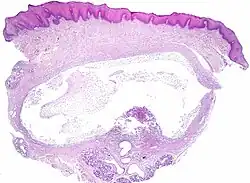

The histologic appearance is similar to mucoceles from other locations. The spilled mucin causes a granulation tissue to form, which usually contains foamy histiocytes.[1] Ultrasound and magnetic resonance imaging may be useful to image the lesion.[4] A small squamous cell carcinoma obstructing the Wharton duct may require clinical examination to be distinguished from a ranula.[5]